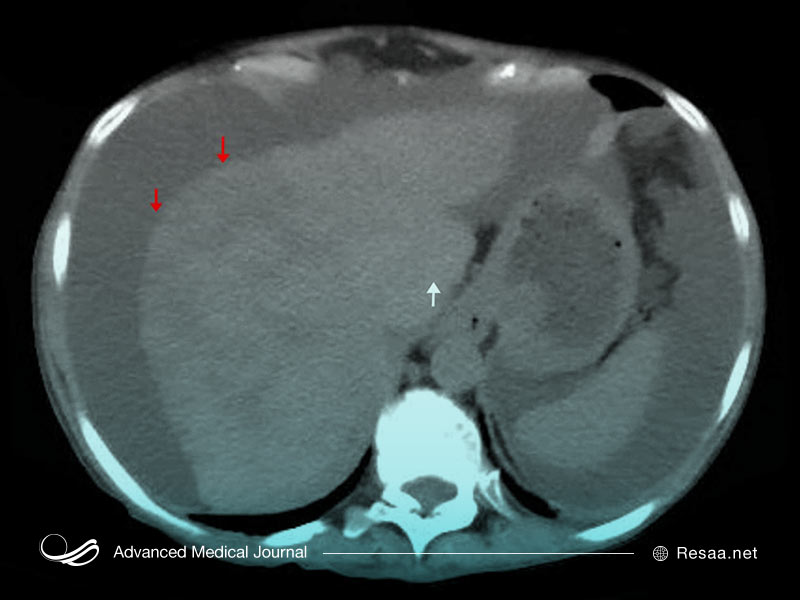

همچنین این امکان وجود دارد که پزشک به منظور کمک به تشخیص بیماری، اسکن تصویربرداری را تجویز کند. این موارد میتواند شامل اشعه ایکس “X-rays”، اسکن MRI و سی تی اسکن “CT scan” باشد. این تصاویر به پزشک شما کمک میکند تا به دنبال ناهنجاری در ساختار استخوان، بافتهای مغز، اندامها و اعصاب باشد.